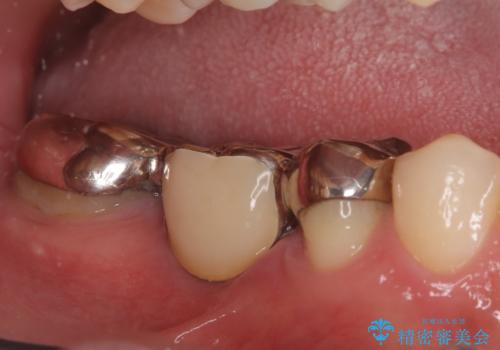

銀歯からセラミックへ。右上奥歯の精密根管治療と審美修復

担当医 河口智英